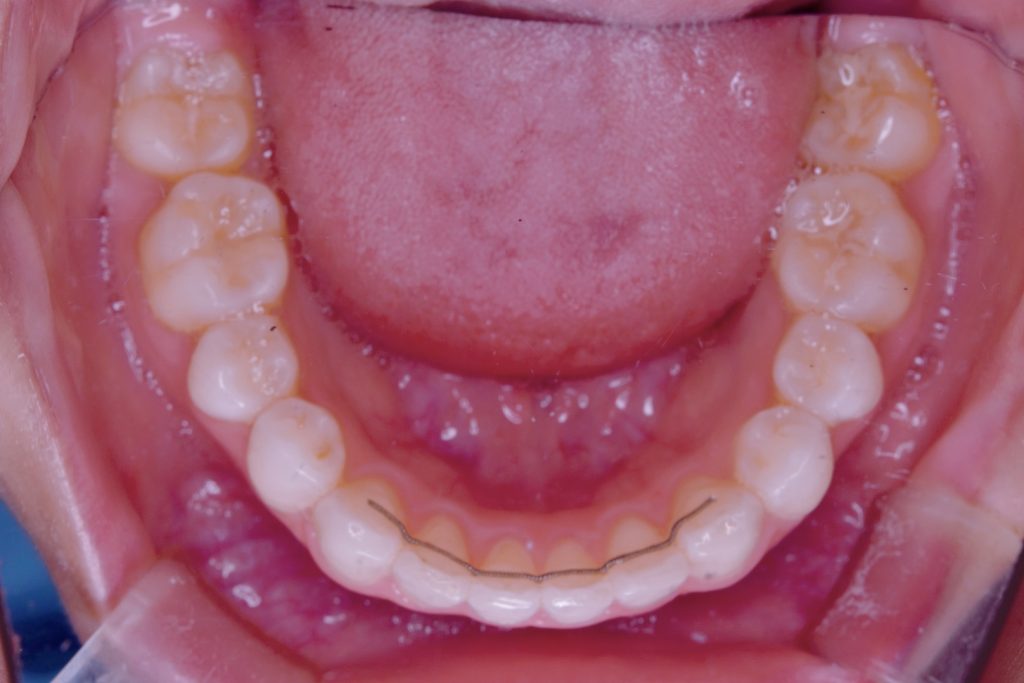

じゃーん!!

⑤フィックスタイプ

今までご紹介したものは取り外しが可能ですが、こちらは固定式になります。

前歯の裏側に使用され、歯に直接接着する保定方法です。一般的に長期間、着けていることが多いです。出来れば一生付けている事をおすすめします。特に元の歯のガタガタが大きかったり舌の癖がある方は後戻りが生じやすいため、フィックスを使用する場合が多いです。

歯並びを保つ力が大きい事やつけ忘れによる後戻りを防げるのが魅力ですが、固定式になるため、汚れが少し溜まりやすくなるデメリットもあります。きちんと歯磨きをしていただければ清潔に保つ事が出来ます。

経年的に接着剤の一部が外れてきてしまったりする事がありますので、クリーニングと一緒に定期的にメンテナンスを受けましょう♫